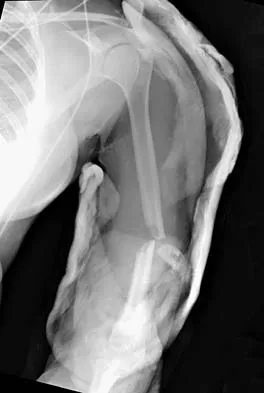

A 32-year-old woman sustained an injury to her left upper extremity in a motor vehicle accident. Examination reveals a 2-cm wound in the mid portion of the dorsal surface of the upper arm and deformities at the elbow and forearm; there are no other injuries. Her vital signs are stable, and she has a base deficit of minus 1 and a lactate level of less than 2. Radiographs are shown in Figures 9a and 9b. In addition to urgent debridement of the humeral shaft fracture, management should include

Explanation

With a severe injury to the upper extremity, the best opportunity for achieving a good functional result for a floating elbow is immediate debridement of the open fracture, followed by internal fixation of the fractures. The ability to do this depends on the patient's physiologic status. In this patient, the procedure is acceptable because she has normal vital signs and no chest or abdominal injuries, and normal physiologic parameters (base excess and lactate) show adequate peripheral perfusion. The surgical approaches will be determined by the associated injury patterns and open wounds. In this patient, the humerus was debrided and stabilized through a posterior approach as was the medial condyle fracture. The ulna was fixed through an extension of the posterior incision and the radius through a separate dorsal approach. Solomon HB, Zadnik M, Eglseder WA: A review of outcomes in 18 patients with floating elbow. J Orthop Trauma 2003;17:563-570.